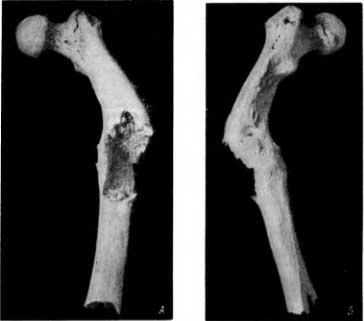

Среди костей из погребений старой Вятки (XVII–XVIII вв.) был обнаружен сросшийся под углом перелом бедренной кости на границе верхней и средней трети.

Перелом осложнился остеомиелитом (рис. 30, А и Б). Видны обширная деструкция (в значительной мере посмертная) на передненаружной поверхности (рис. 30, А) и 2 свищевых хода на внутренней поверхности бедренной кости (рис. 30, Б). Это — травматический остеомиелит. Перелом бедра, осложненный остеомиелитом, представлен и на рис. 31 (из погребения в старой Вятке).

Рис. 30. А — перелом бедра, осложненный остеомиелитом (вид сзади и снаружи); Б — видны два свищевых хода на уровне дистального конца linea pectinea (вид спереди и с медиальной стороны).

Рис. 31. Сросшийся перелом бедра, осложненный остеомиелитом, с двумя свищевыми ходами.